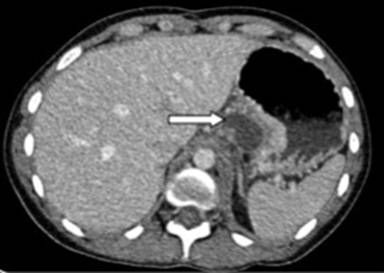

A twenty-two-year-old female with a history of alcohol-induced chronic pancreatitis was admitted with abdominal pain and dysphagia. On examination she had a midline laparotomy scar from previous abdominal surgery and marked tenderness in the epigastric area on palpation but the examination was otherwise unremarkable. Her blood tests revealed a white cell count of 14.0, haemoglobin of 11.7, platelets of 458, CRP of 4, amylase of 279, albumin of 39, bilirubin of 10, ALP of 93 and ALT of 21. Her urea and electrolytes were unremarkable. A CT scan performed during this admission revealed a large cyst arising from the body and tail of the pancreas extending posteriorly to the stomach and tracking behind the oesophagus and into the mediastinum (Figures 2 and 3). Cyst fluid aspirated under EUS guidance yielded an amylase level of 20,000 confirming this to be a pancreatic pseudocyst. The EUS also showed calcification in the pancreas in keeping with chronic pancreatitis. Although aspiration provided temporary resolution of her symptoms, the patient experienced recurrence of pain and discomfort. At laparotomy a retrogastric pseudocyst communicating with the mediastinum was clearly identified on intraoperative ultrasound scan. An anterior gastrostomy was performed and intraoperative ultrasound was again used to locate the pseudocyst. A posterior wall gastrostomy was created to enter the cyst and the cyst wall was sent for histology. Intraoperative contrast study confirmed the communication with the mediastinal cavity. A surgical cystogastrostomy and a feeding jejunostomy were performed. The patient had an uneventful recovery.

Figure 3. Case #2. Axial CT image of the patient in figure 1 acquired in portal phase following intravenous contrast medium. This demonstrates the component of the pseudocyst abutting the pancreas (arrow). |